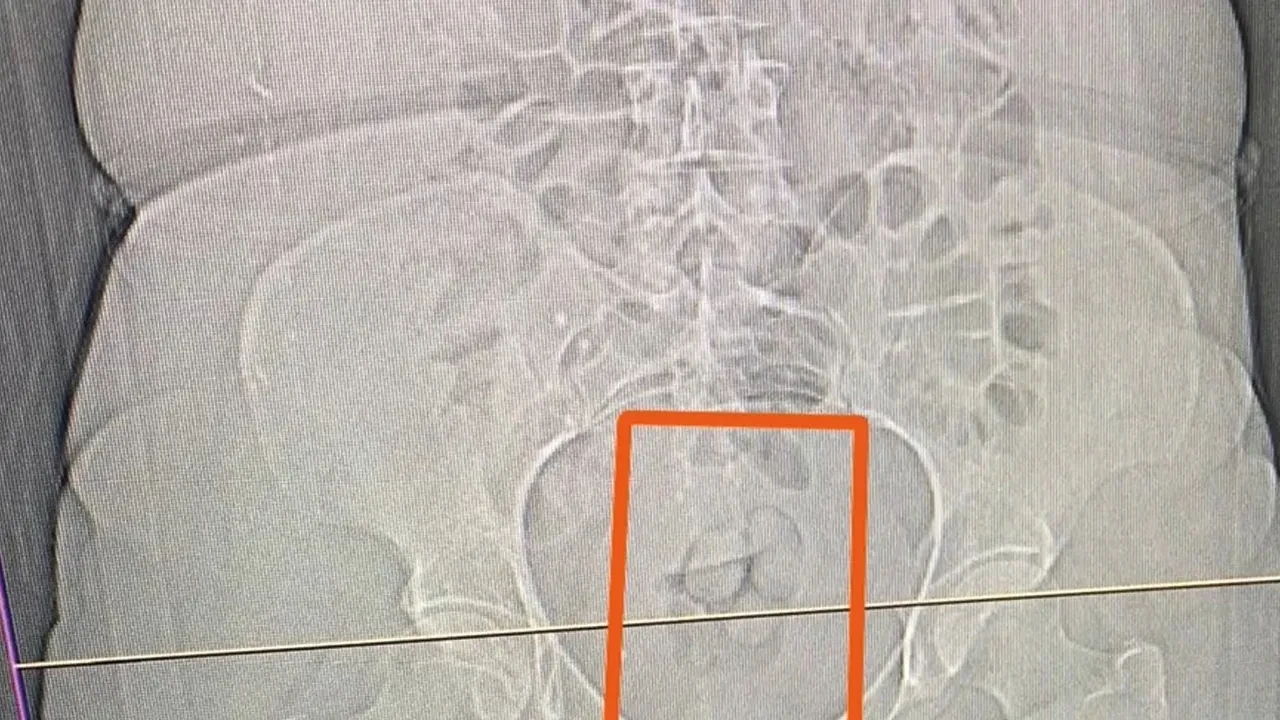

Araç içerisinde yapılan aramada 16,40 gram metamfetamin ve 2 adet cam aparat (pipe) ele geçirildi. S.S. isimli şahısın şüpheli görülmesi üzerine çekilen tomografi neticesinde şahsın midesinde yabancı maddeler tespit edildi. Yapılan iç beden muayenesi sonucunda ise şahıstan 21,39 gram metamfetamin maddesi ele geçirildi.